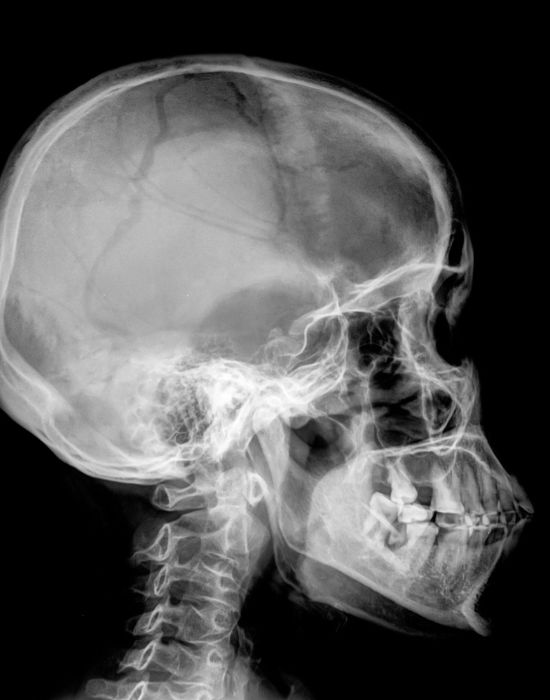

Рентгенодіагностика щелепно-лицевої ділянки. Що повинен знати рентген-лаборант?